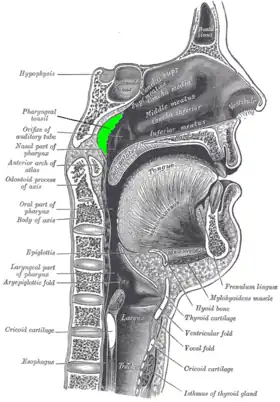

Location of the adenoid | |

In anatomy, the pharyngeal tonsil, also known as the nasopharyngeal tonsil or adenoid, is the superior-most of the tonsils. It is a mass of lymphatic tissue located behind the nasal cavity, in the roof of the nasopharynx, where the nose blends into the throat. In children, it normally forms a soft mound in the roof and back wall of the nasopharynx, just above and behind the uvula.

The adenoid is a mass of lymphatic tissue located behind the nasal cavity, in the roof of the nasopharynx, where the nose blends into the throat. The adenoid, unlike the palatine tonsils, has pseudostratified epithelium.[2] The adenoids are part of the so-called Waldeyer ring of lymphoid tissue which also includes the palatine tonsils, the lingual tonsils and the tubal tonsils.